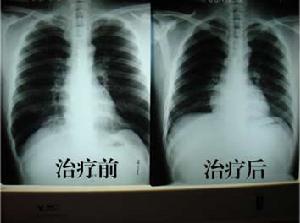

X線檢查

早期可無明顯改變,反覆急性發作者可見兩肺紋理增粗、紊亂呈網狀或條索狀及斑點狀,陰影以下肺野為明顯,此系由於支氣管管壁增厚、細支氣管或肺泡間質炎症細胞浸潤或纖維化所致。

治療

對細菌性急性支氣管炎患者,可以使用相應的抗生素;在大多數情況下,急性支氣管炎是由病毒引起的,幾天后將自行痊癒,無需抗生素;如懷疑合併有細菌感染,抗生素也可以考慮;避免吸菸。急性發作期的治療原則是控制感染,祛痰平喘為主。